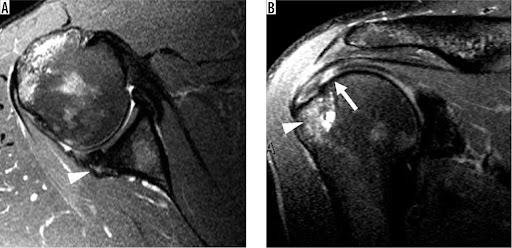

회전 근개(힘줄) 파열의 MRI

MRA (Magnetic Resonance Arthrography)입니다

그 방법은 어께 관절 부분에 염색약을 주사한 후, MRI 촬영을 하면

어께 회전 근개 파열이 있는 곳으로 염색약이 새어 나가서

어께 관절의 정확한 이상 부위를 쉽게 알 수 있도록 하는 것입니다

위의 그림에서 하얗게 보이는 부분이 염색약 입니다